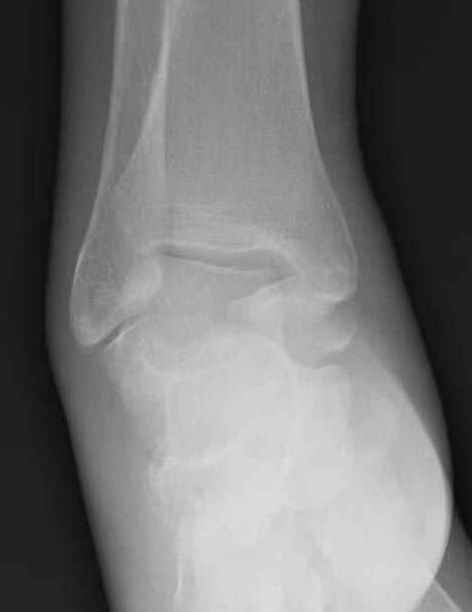

Уважаемые участники русского Ортофорума, поздравляю всех со всеми прошедшими праздниками: Новым годом, Рождеством, Hanukkah, Kwanzaa, желаю участникам всего наилучшего и здоровья.Повреждение таранной кости.Больной 81г автоавария, повреждение таранной кости, здесь снимки. Какие рекомендации?Djoldas Kuldjanov, MDDepartment of Orthopedic SurgerySt. Louis University Medical Center

Вдогонку по поводу перелома таранной кости, больная 81, не страдает диабетом, перелом закрытый, в первый же день поступления ограничились временным наружным фиксатором (как на снимке).

Планировалась открытая фиксация после спадения отека, но больная пожелала лечиться по месту жительству в другом штате..

Примеры на снимке...